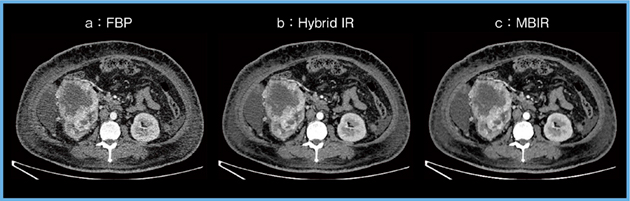

Aquilion Precisionにて,腹部の動脈相をSHR(super high resolution)モードで撮影し,Hybrid IRとMBIRで再構成したところ,いずれもノイズが多い画像であった(図5 a,b)。超高精細CTは,高い空間分解能が得られることが大きな特徴であるが,腹部の場合,スライス厚を0.25mmまで薄くするとノイズが非常に増加し,超高精細CTのメリットを十分に享受することができない。

しかし,同じ症例をDLRであるAiCEで再構成を行うと,ノイズの低減した非常に明瞭な画像を得ることが可能となった(図5 c)。AiCEを用いることで,腹部領域における超高精細CTのノイズを低減することができ,超高精細CTの最大のポテンシャルを引き出せる可能性があると期待している。

図5 腹部領域における超高精細CT